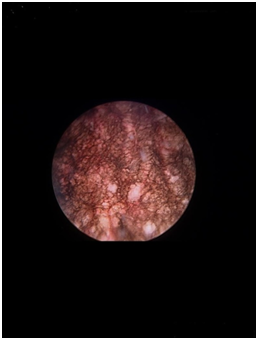

A 47-year-old woman was referred to our Department of Urology with abdominal pain, urgency and urinary incontinence. The urine sediment showed microscopic hematuria and urine culture was negative. Patient’s past medical history is positive for recurrent urinary tract infections and two caesarean sections. CT-scan showed no evidence of disease. Cystoscopy revealed black-pigmented urothelium on the posterior wall of the bladder (Figure 1). Urine cytology showed normal urothelial cells with pigmentation. Cold cup biopsies of the pigmented urothelium demonstrated normal urothelial cells with black pigments focally present in the cytoplasm. There were no melanocytes identified in Hematoxylin and Eosin stained sections (Figure 2), or in the additional immune histochemical stainings for melanocytic markers (S-100, Melan-A, SOX10 and HMB-45). Special histochemical staining was performed; the Schmorl staining (Figure 3) and Fontana Masson for detecting melanin were positive. Periodic Acid Schiff for detecting lipofuscin and Perls stain for detecting hemosiderine were negative. The CD68 staining showed macrophages in the superficial lamina propria with melanin pigment in the cytoplasm. Also loose melanin pigment deposits could be appreciated between these macrophages. These cystoscopic and histopathologic findings were diagnostic for bladder pigmentation due to melanosis vesica.

Figure 1 wall of the bladder.